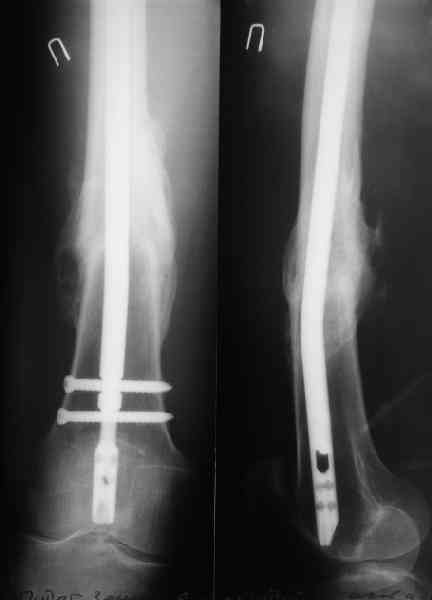

Как обещал, выкладываю рентгенограммы нашего пациента.

Пациенту М., 30-ти лет, 1,5 года назад в одной из московских больниц был выполнен остеосинтез бедренной кости штифтом UFN (диаметр штифта 9 мм).

К нам больной поступил с признаками ложного сустава бедренной кости, перелома

штифта и дистального блокирующего винта (images 1,2,3).

27 марта выполнено удаление блокирующих винтов (сломанный винт пришлось высверливать цапфен-бором), сломанного штифта (дистальный фрагмент удален через канал, образованный разверткой из коленного сустава - image 4),

рассверливание костно-мозгового канала, реостеосинтез штифтом UFN (при проведении штифта в дистальном отломке мы использовали поляризующий винт, диаметр штифта 10 мм). После операции в связи гемартрозом дважды (на 1 и 3 сутки) выполняли пункцию коленного сустава. Сейчас признаков скопления жидкости в полости сустава нет. Послеоперационные рентгенограммы - images 5, 6, 7.